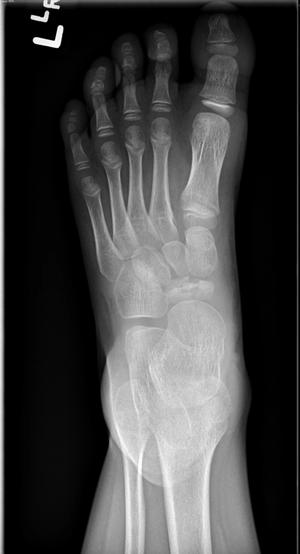

Image IQ Quiz: Pediatric Patient Presents with Foot FindingByVaibhav Khasgiwala, M.D.March 31st 2021What is your diagnosis for a pediatric patient who presents with findings on a foot radiograph?